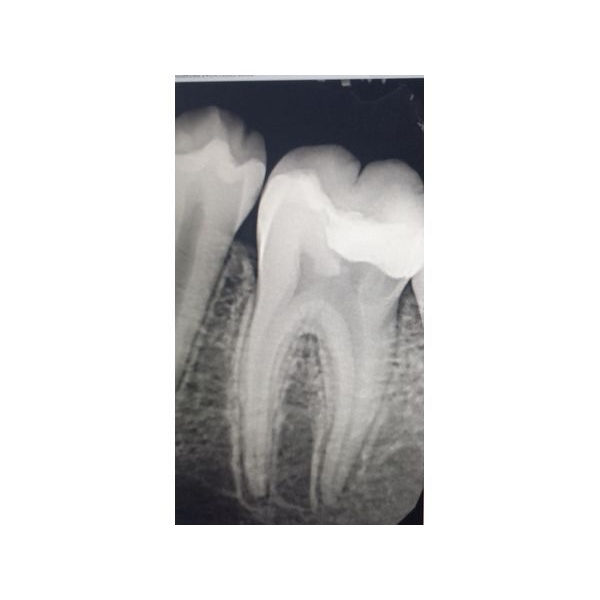

На прицельной контактной рентгенограмме на окклюзионно-дистальной (верхней дальней) поверхности видно пломбу — обширное просветление твёрдых тканей зуба, сообщающееся с полостью зуба. Корни, согласно снимку, находятся в стадии формирования закрытой верхушки.

Определили рабочую длину корневых каналов и сделали рентгенографию, чтобы её подтвердить. Затем каналы обработали, высушили и запломбировали. С помощью рентгенографии проверили, что корневые каналы запломбированы полностью до физиологической верхушки.